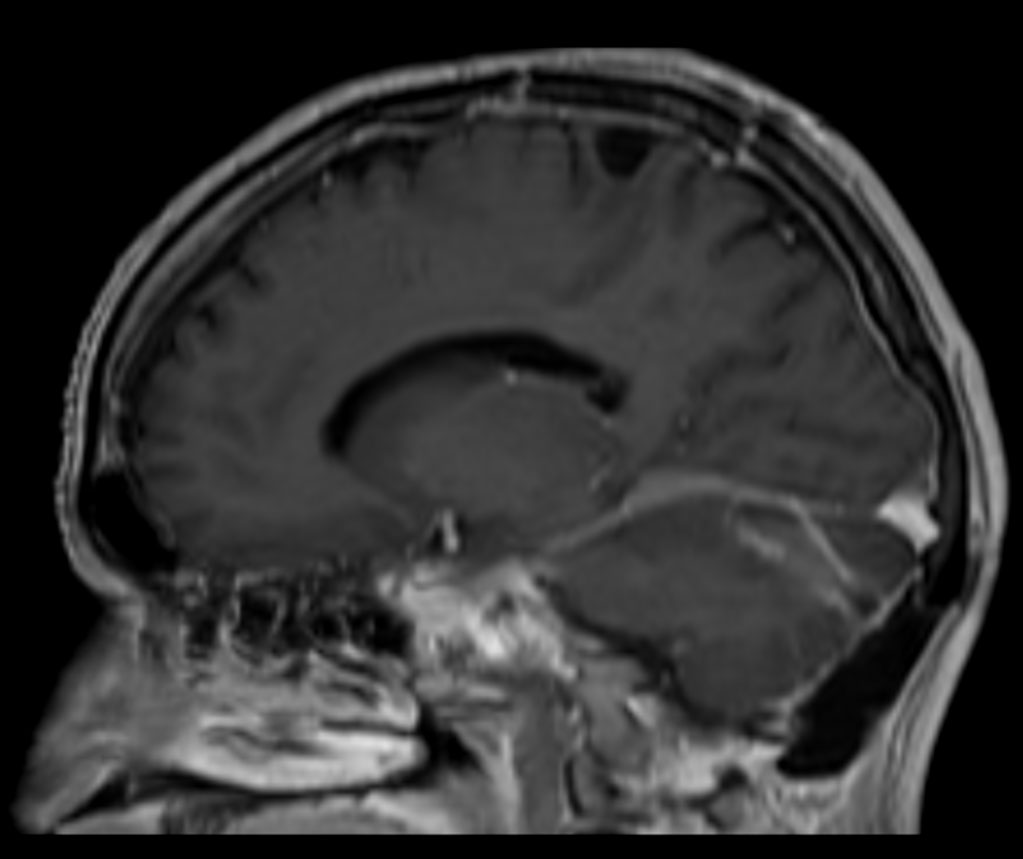

3D T1W FFE post contrast (sagittal reformat)